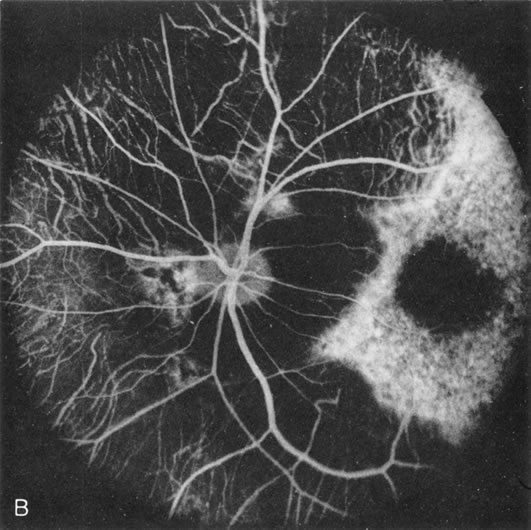

In the early stages of choroideremia, before choroidal atrophy is funduscopically obvious and when the picture resembles RP, FA indicates diffuse choroidal atrophy throughout the entire retina. Only the macular area remains preserved (Fig. 4A and B).

Fig. 4. Choroideremia and choroideremia carrier. A. The choroidal atrophy in this affected male is not apparent in the fundus. B. However, the angiogram shows diffuse atrophy of the choriocapillaris with persistent visualization of the larger choroidal vessels. C. This carrier female has peripapillary choroidal atrophy and diffuse pigment mottling. D. The patchy areas of focal choroidal atrophy that occasionally occurs in carriers is evident on angiography.

The typical carrier female, with focal or diffuse pigment mottling, does not show choroidal atrophy. However, a few carrier females have a more severe form with focal areas of choroidal atrophy. The presence of these areas, and possible progression, can be documented by FA (Fig. 4C and D). These carriers exhibit a mosaicism, which is explained by the Lyon hypothesis of random X-chromosome inactivation.